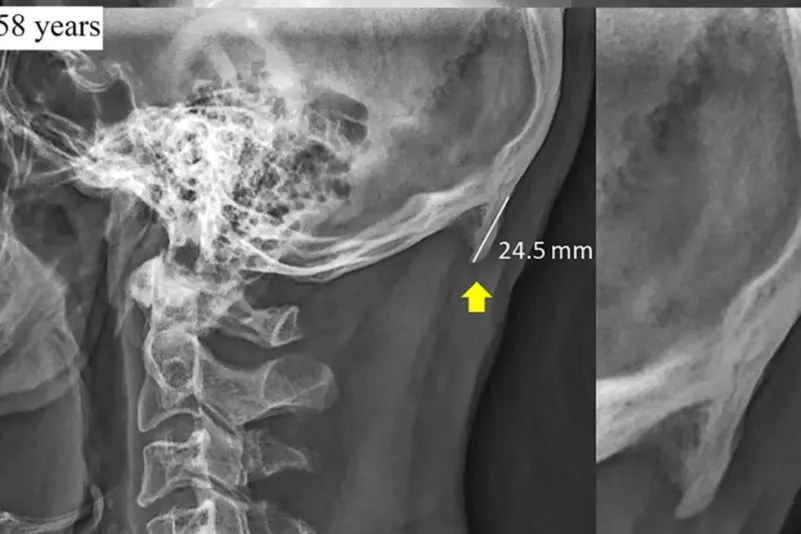

Das "Handy-Horn" wächst am Nackenansatz.

Gemeint ist eine Hornwucherung direkt über dem Nacken. Bei Glatzen könne man das Horn sehen. Wenn man selbst eines hat, könne man es ertasten.

Besonders auffällig war die Tatsache, dass jeder vierte Mensch zwischen 18 und 30 Jahren die Knochenspitze am Hinterkopf zeigte. Shahar vertritt die Auffassung, dass diese auf die neueste Besessenheit von Smartphones & Co. zurückzuführen ist. Sobald man zum Handy greift, beugt man den Kopf nach vorne. Diese Haltung ist nicht natürlich.

Vor Shahars Studie beschäftigten sich bereits auch Forscher in Indien im Jahr 2012 mit dem Phänomen. Von den unzähligen Schädeln, die dort untersucht wurden, wies lediglich einer das Handyhorn auf. Und es war mit acht Millimeter derart gering, dass es in Shahars derzeitigen Studien keine Erwähnung gefunden hätte. Nach seinen Forschungen war die größte Wucherung 30 Millimeter lang.